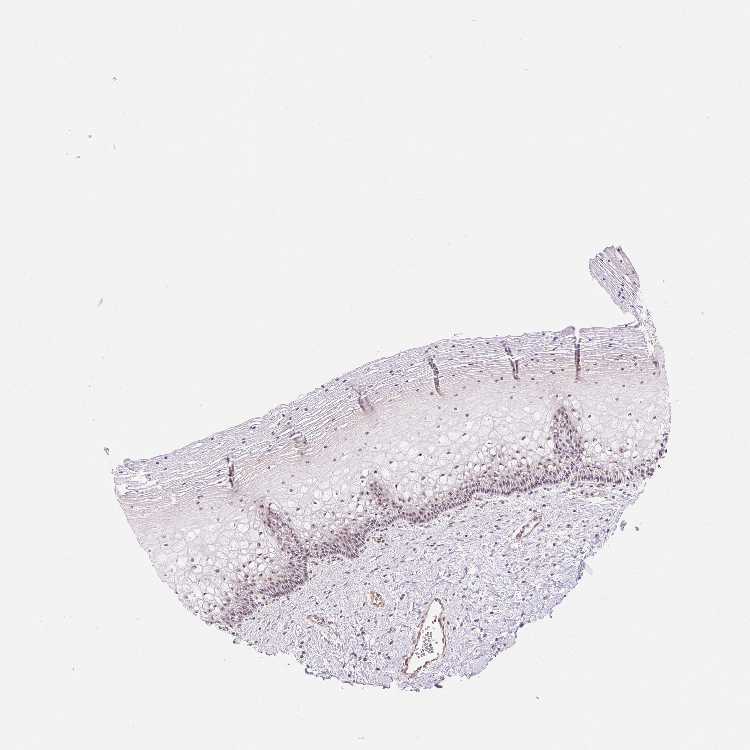

CERVIX - Antibody stainingi

Antibody staining in the annotated cell types in the current human tissue is reported as not detected, low, medium, or high, based on conventional immunohistochemistry profiling in selected tissues. This score is based on the combination of the staining intensity and fraction of stained cells.

Each image is clickable and will lead to virtual microscopy that enables deeper exploration of all samples and also displays staining intensity scores, fraction scores and subcellular localization as well as patient and tissue information for each sample.

Antibody HPA055955

Glandular cells Medium

Squamous epithelial cells Medium